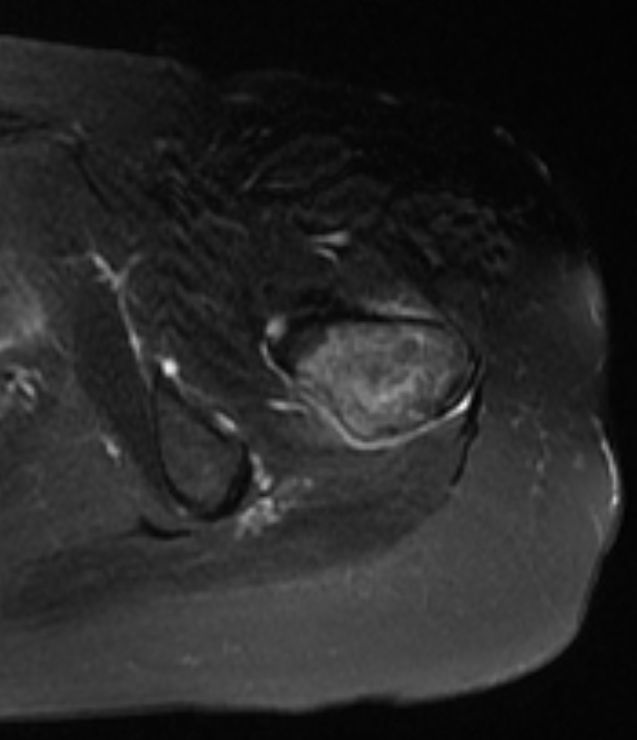

Femur | 58-jährige Frau mit Mammakarzinom links vor 14 Jahren und Mammakarzinom rechts vor 2 Jahren. Seit 4 Monaten Schmerzen im linken Oberschenkel. Jetzt Lungenmetastasen, osteoplastische Metastasen im LWk1 bis LWK4 sowie eine Osteolyse im linken Femur. | ||||||||||

MRT T2 KM Fett - saturiert![]() |

MRT T2 KM Fett - saturiert![]() | ||||||||||

MRT T1 KM Fett-saturiert![]() |

MRT T1 KM Fett-saturiert![]() | ||||||||||